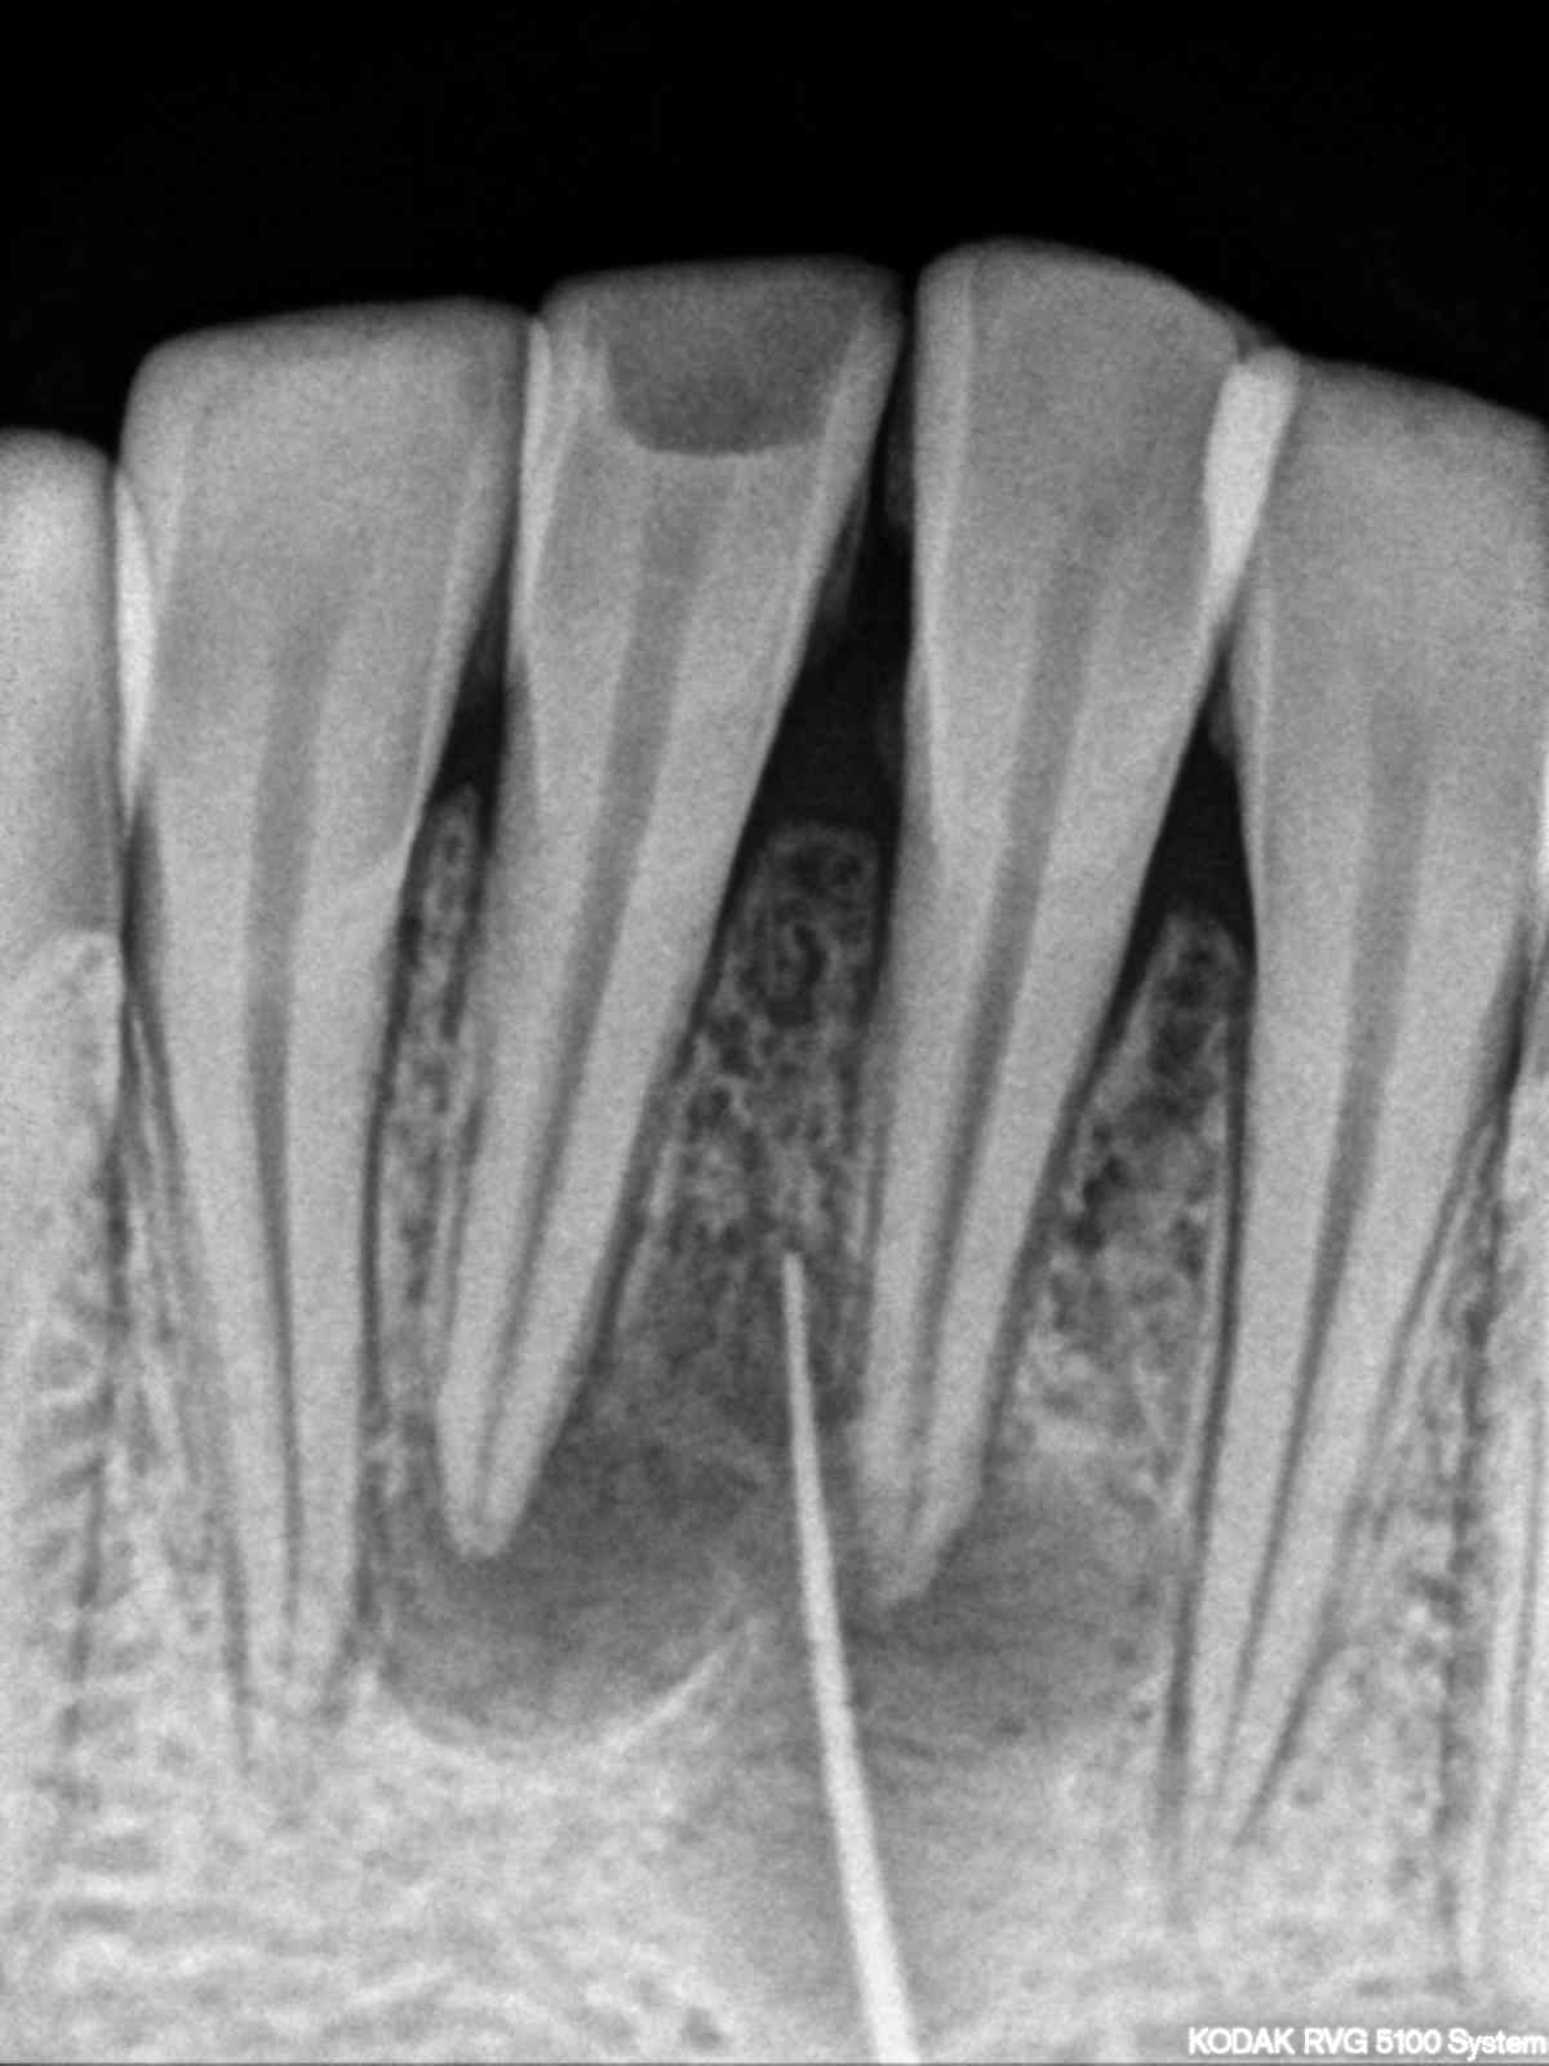

The patient had cutaneous opening of size 5mm × 6mm with purulent discharge in submental region. Patient had undergone three surgical excisions and multiple antibiotic regimens. Patient had a history of trauma due to fall six years back. A 30 number standard gutta-percha was used to trace the sinus tract and dental origin was confirmed radiographically. The tract led to in-between the root canal apices of both mandibular incisors. Treatment included non-surgical endodontic treatment with both mandibular central incisors and antibiotic coverage following bacterial culture of discharge. The pus culture showed Streptococcus anginosus which was found to be sensitive to penicillin. Patient was kept on 1-week course of oral amoxicillin-clavulanate along with root canal therapy.

The cutaneous sinus healed following root canal treatment and antibiotic coverage. On an 8-year follow-up skin of sub-mental region appeared normal and peri-apical healing with both mandibular central incisors was evident radiographically. Cutaneous lesions on face may be of dental origin. A cross referral between dentists, physicians, surgeons, and dermatologists should be considered in such cases.